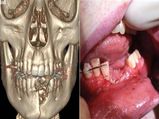

ಇ ಸಿಗರೇಟ್ ಸ್ಫೋಟಿಸಿ ಹುಡುಗನ ಬಾಯೊಳಗಿನ ಹಲ್ಲುಗಳೇ ಛಿದ್ರ!